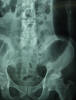

APR Cálculo renal coraliforme